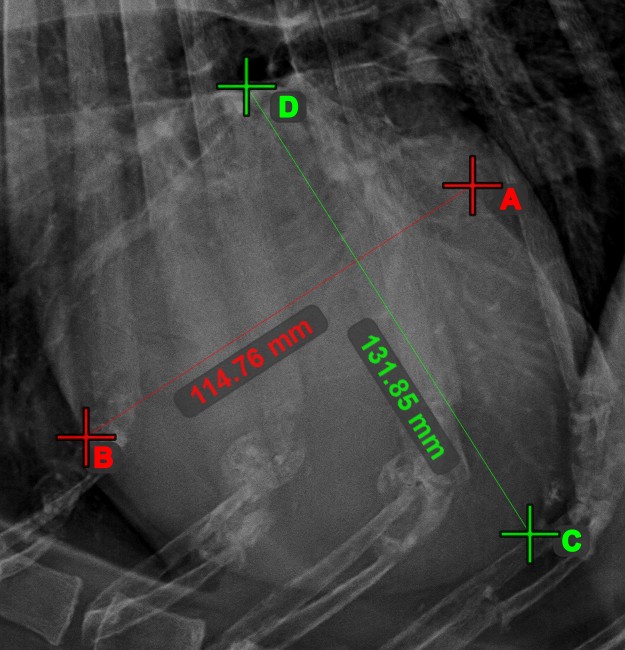

Linienkreuzung¶

Lokalisieren und markieren Sie schnell und präzise den Schnittpunkt zwischen zwei vorhandenen Linien mit dem Werkzeug Linienkreuzung

.

Wählen Sie das Werkzeug aus der linken Symbolleiste aus und weisen Sie es einer der verfügbaren Maustasten zu. Wählen Sie zwei bereits in der Szene gezeichnete Linien aus, um die Messung abzuschließen. Der Schnittpunkt der Linien wird automatisch berechnet und in der Szene markiert. Der Schnittpunkt zweier Linien wird stets mit dem Buchstaben X markiert.

Informationen

Wenn sich zwei Linien nicht direkt schneiden, wird der Schnittpunkt ihrer verlängerten Projektionen in der Szene markiert.